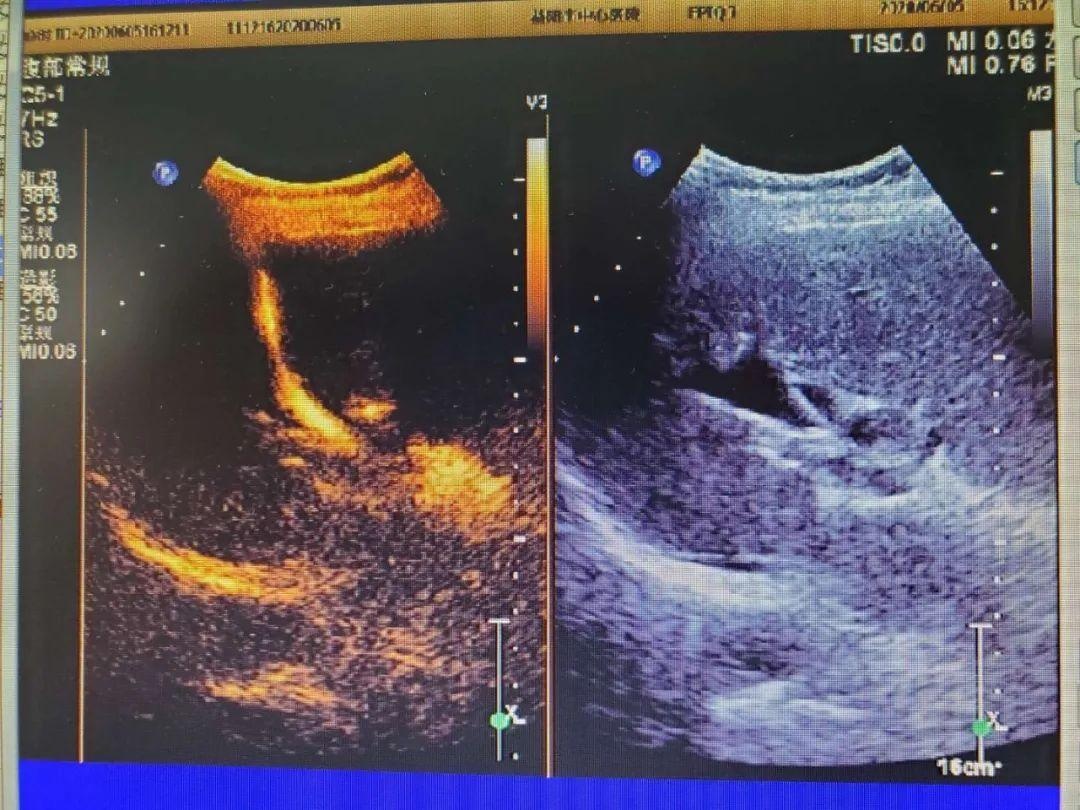

图3 肾活检

1、 多部位实性肿块组织活检,如肝脏、肾脏,乳腺、甲状腺、浅表等部位肿块活检。

2、 肝、肾等弥漫性病变的组织活检进一步明确诊断。